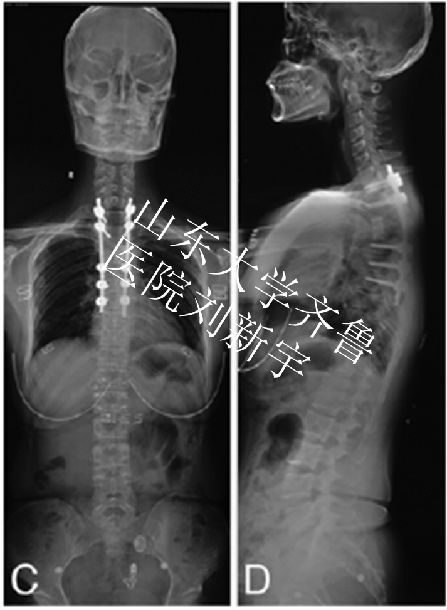

典型病例2:脊柱侧凸

典型病例3:先天性脊柱侧凸

术前CT 术后2年可见畸形矫形满意